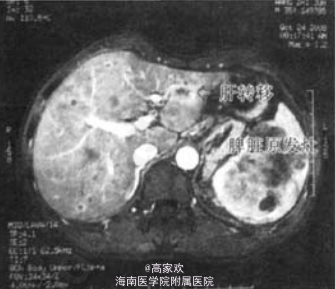

入院查体:全身浅表淋巴结未及肿大,皮肤巩膜无黄染。腹平软,无压痛,脾脏肋下2 em,质韧,轻度压痛。肝脏肋下未及。AFP、CA199、CEA、肝功能正常。 B超提示:肝脏大小、形态正常,肝内可见多发低回声占位,界清。内部回声欠均,部分呈“牛眼征”,最大位于右后叶,约11mmx8mm。脾脏大小形态饱满,被膜完整,脾实质内可见一范围约100 mmx62 mm的偏强回声占位.界清.内部回声欠均匀.CDFI示血流信号丰富。 上腹部MRI平扫+增强显示:脾脏体积增大.内部巨大肿块影。最大径约10 cm,内部信号混杂TIWI呈等低混杂信号,q'2WI呈高低混杂信号.增强扫描后呈不均匀显著强化。肝脏实质内可见多发结节影,个案报告·增强扫描后可见环形强化.最大直径约1cm。肝门、腹膜后未见明确肿大淋巴结

术前诊断:1、脾脏占位:恶性肿瘤可能;/2、肝内多发占位:转移可能。 为进一步明确诊断行诊断性脾切除术。术中见:腹腔内无明显腹水,腹腔无种植。肝脏表面可见多发结节,灰白色,质硬,最大约1cm,有一结节位于左肝外叶边缘:脾脏肿大.大小约12 cmx11cmX7 cm,包膜隆起.脾脏实质内町扪及一较大实性占位。质软。其他脏器未见明显异常.周围淋巴结未见明显肿大。行脾切除术,同时切除肝左外叶边缘处小结节送病理检查。 术后病理:脾脏血管肉瘤并肝转移。